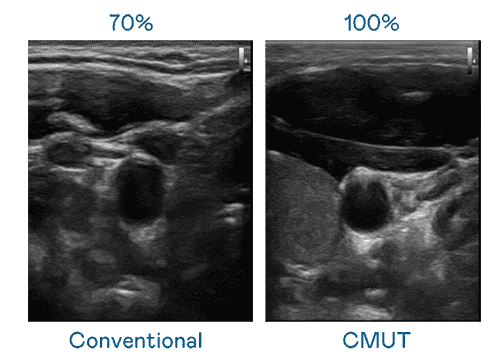

CMUT 技术是一种用电容式微机电元件来产生超音波讯号的技术。。与传统 PZT 压电式技术相比,,,,CMUT 频宽增加 30%,,更宽频的超音波讯号让影像解析度大幅提升,,是实现高影像品质医疗超音波扫描、、、促进精准医疗发展的关键技术。。。

大频宽带来超清晰影像

超音波影像的解析度高低,,,,首先取决于探头能发出的讯号频宽。。。。尊时凯龙 CMUT 可提供高清晰的超音波讯号,,,,提供高频宽、、、、高灵敏度、、、影像纹理细节更高的超音波影像,,,,协助医护人员缩短影像判读时间及利用精准的医疗影像进行诊断。。。